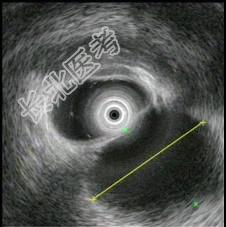

- 单项选择题1.超声内镜如图,B超引导穿刺检查示渗出液,淀粉酶265U/L。此患者的诊断 ( )

A、急性胰腺炎伴假性囊肿

B、慢性胰腺炎伴假性囊肿

C、胰腺囊腺癌

D、腹腔积液

E、腹腔血肿